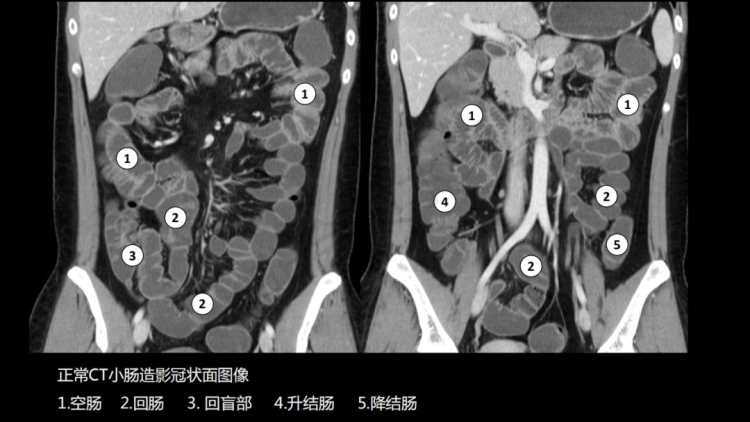

CT小肠造影(CT enterography,CTE)是患者口服或经小肠导管注入对比剂使小肠腔充盈足量对比剂后,经多排螺旋CT增强扫描,并将图像进行后处理,使肠腔、肠壁、肠系膜、腹腔内血管、后腹膜及腹内实质脏器多方位显示出来的技术。临床证明,CT小肠造影(CT enterography,CTE)可精确的判定小肠肿瘤的数目,监测出小肠早期肿瘤,可作为小肠肿瘤定位及诊断的首先检查方法。

CTE简便易行,无明显并发症,不仅能观察肠腔、肠壁、肠外淋巴结、肠系膜、肠系膜血管关系以及毗邻结构等,还可以精确显示粘膜病变、肠壁增厚及肠外并发症,可准确判断小肠肿瘤的浸润深度。适用于多种小肠病变,全腹部扫描能及时发现肿瘤转移情况,有助于临床更准确的把握肿瘤术前分期,能够为患者制定最优治疗方案,带来更好的预后。